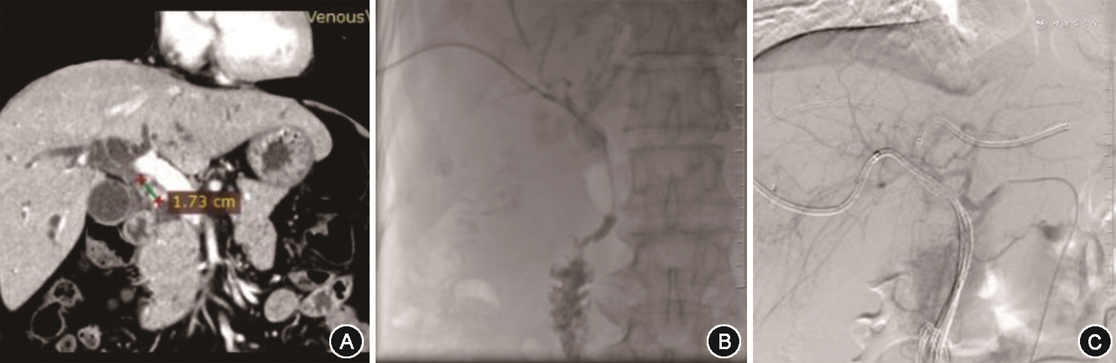

4. 预测模型的验证:训练组中患者6个月生存率列线图预测模型的AUC为0.925(95%CI:0.888~0.963)、1年AUC为0.921(95%CI:0.877~0.964)、2年AUC为0.974(95%CI:0.957~0.993);验证组中患者6个月、1年、2年AUC分别为0.951(95%CI:0.911~0.991)、0.917(95%CI:0.857~0.977)、0.848(95%CI:0.737~0.959),AUC均>0.8,显示该预测模型区分度良好,有着较高的准确性(图1、2)。

训练组和验证组6个月、1年校准曲线走形均与理想曲线基本吻合,2年校准曲线拟合度则欠佳,说明该模型预测胆管癌患者短期生存率与实际生存率有较高的一致性(图3、4)。训练组DCA曲线显示列线图模型6个月和1年的临床净收益较高,临床预测有效性较好,2年的净收益相对较低(图5)。胆管癌患者介入治疗前后的影像学表现见图6。